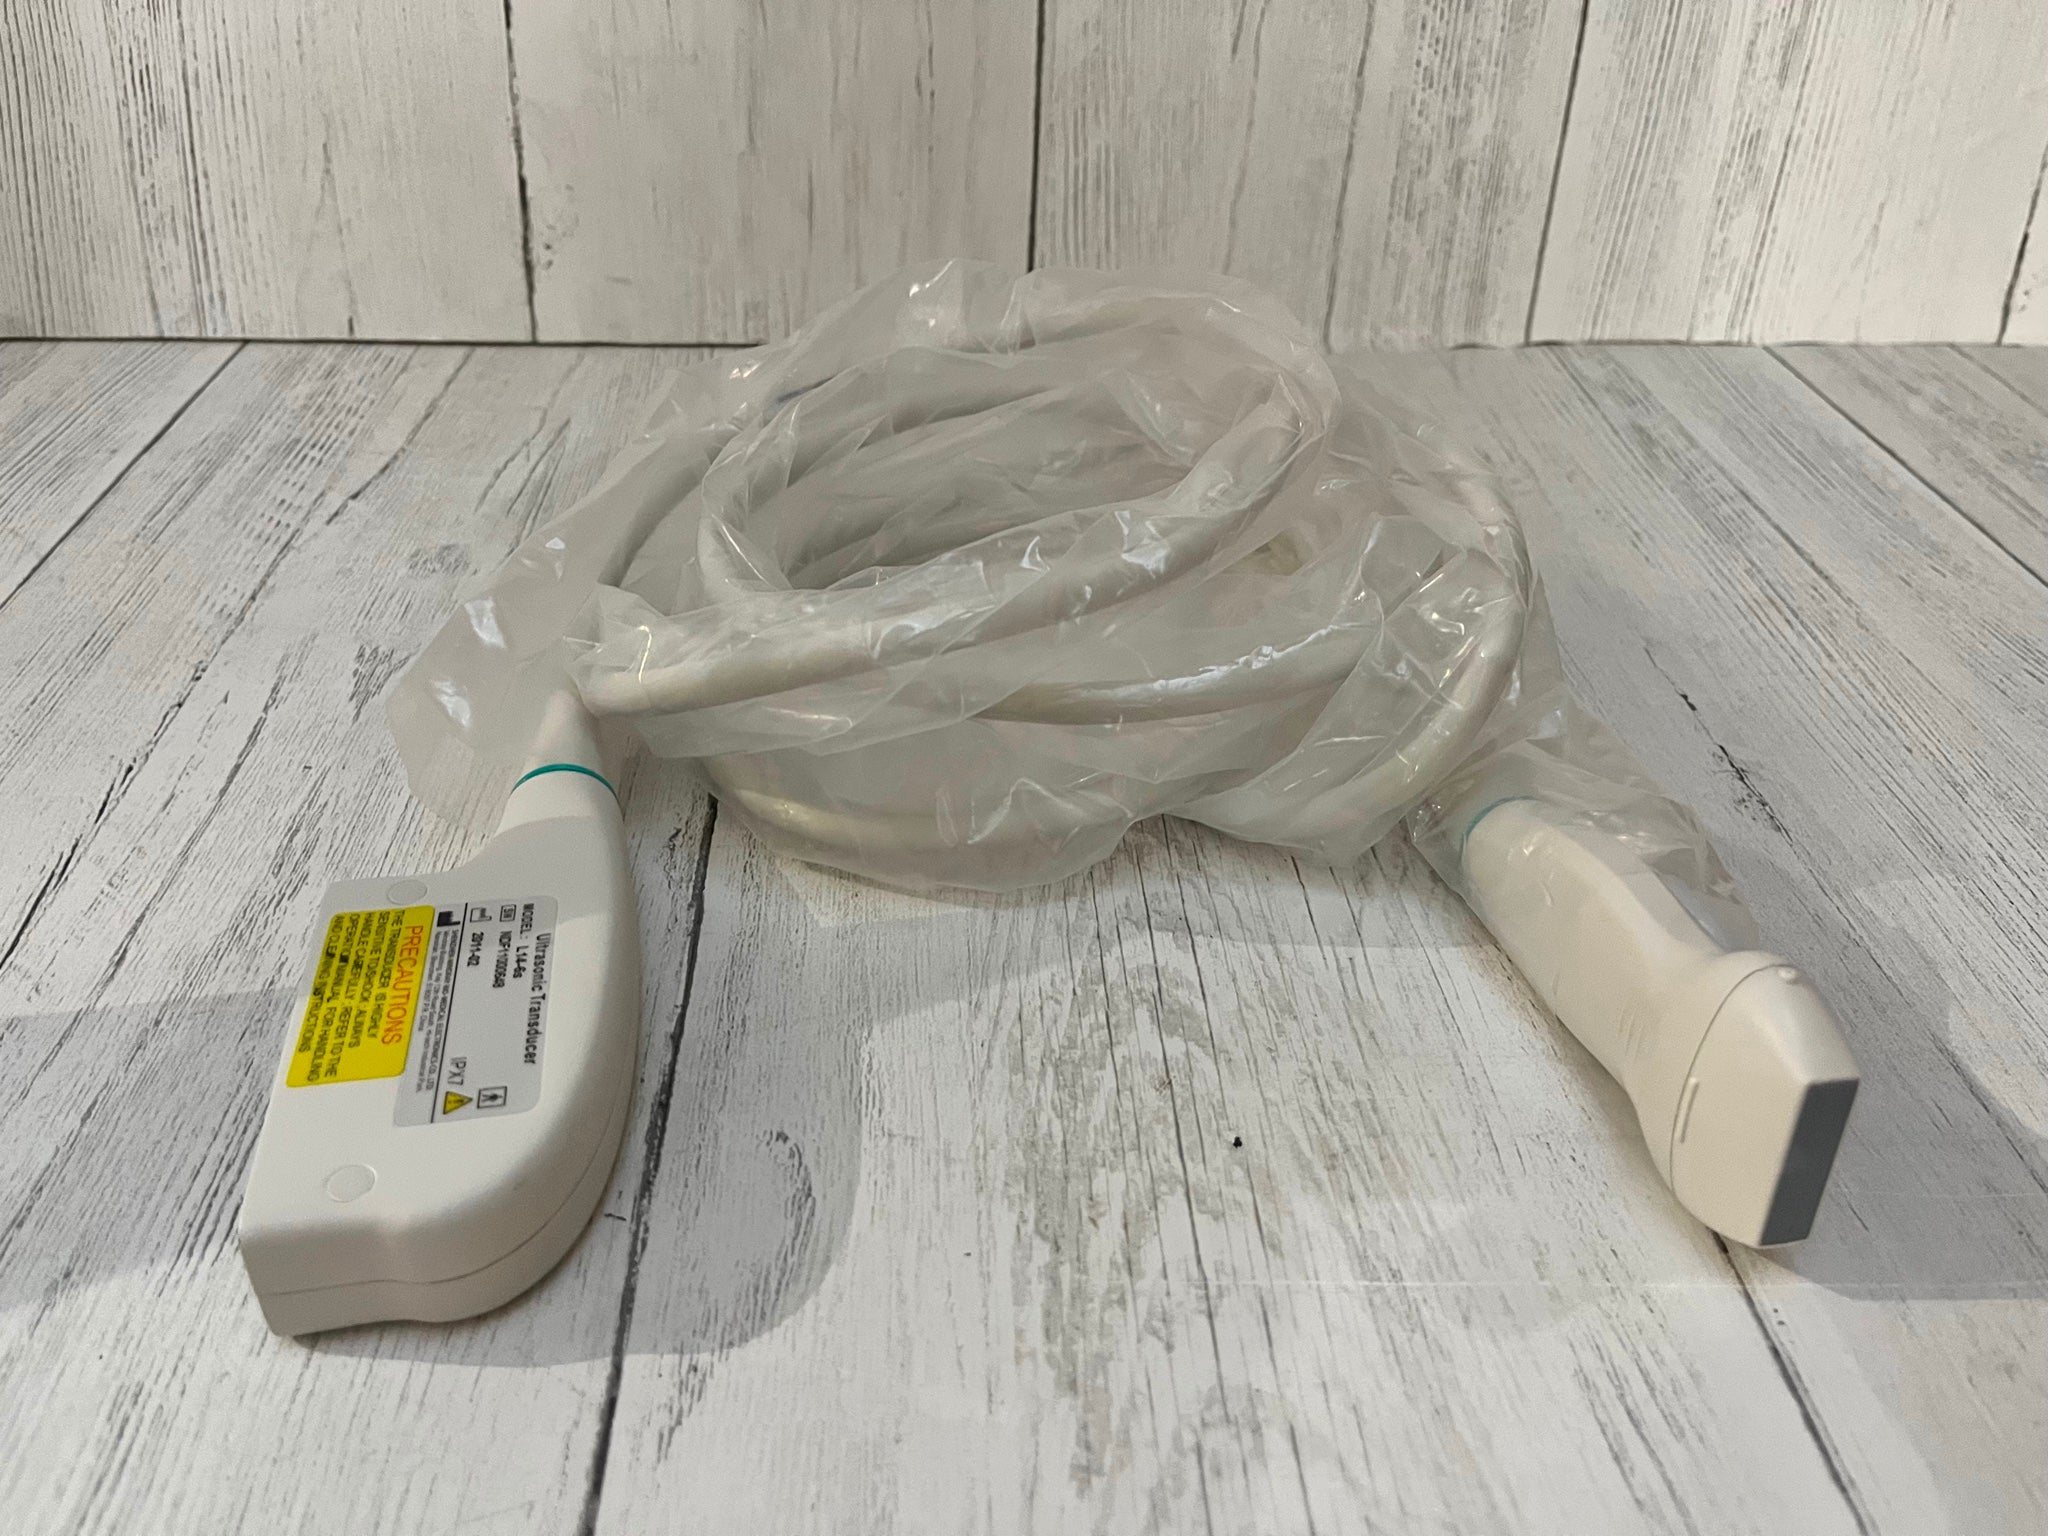

Philips X7-2 Ultrasound Probe Transducer

Sale price$ 1,392.60